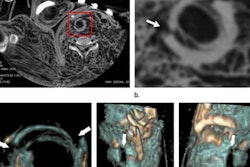

3D-rendered image shows the exit wound of a ballistic projectile in a neutral bloodless manner favored by juries and investigators. Image courtesy of Dr. Thomas Ruder.Ruder often uses a side-by-side comparison of antemortem images from local hospitals with postmortem CT images to identify subjects. Postmortem CT images may be reformatted to match almost any type of antemortem images, even high-quality ultrasound, he noted.